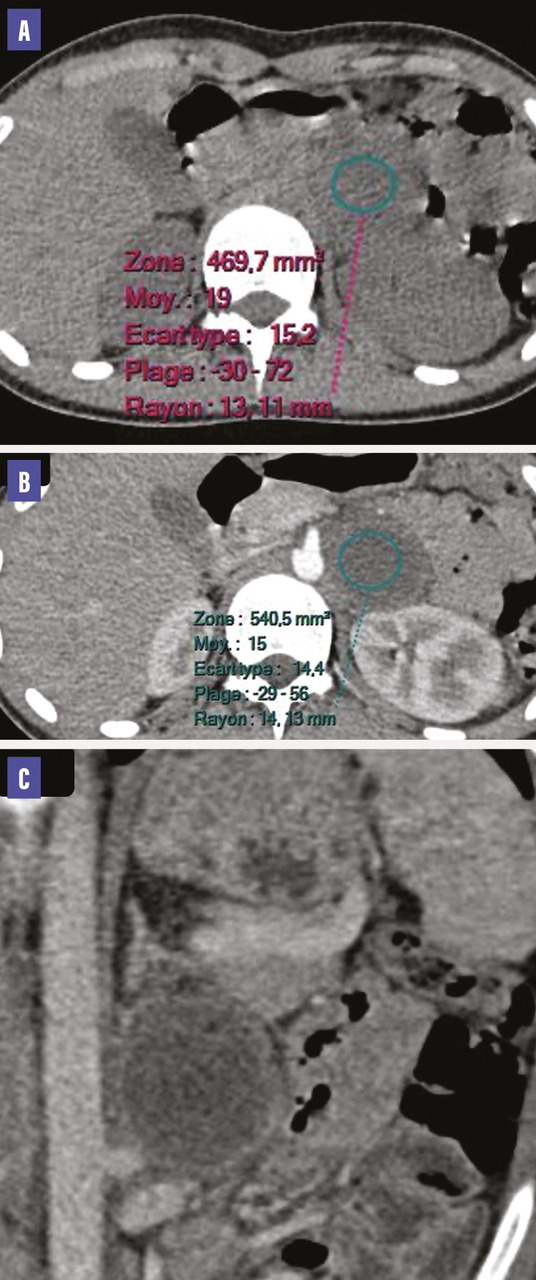

Le scanner réalisé montre une intégrité des glandes surrénales avec présence d’une masse rétropéritonéale gauche, bien limitée, de contours réguliers, de 45 x 40 mm, de densité liquidienne, à paroi épaisse et régulière rehaussée après contraste (figure). L’étude histologique est en faveur d’un paragangliome sans signes de malignité.

Généralement, il s’agit d’une masse bien limitée, hypervascularisée, mais pouvant être kystique, nécrosée en son centre ou calcifiée.2

Les formes malignes ont un caractère infiltrant et présentent des remaniements nécrotico-hémorragiques.